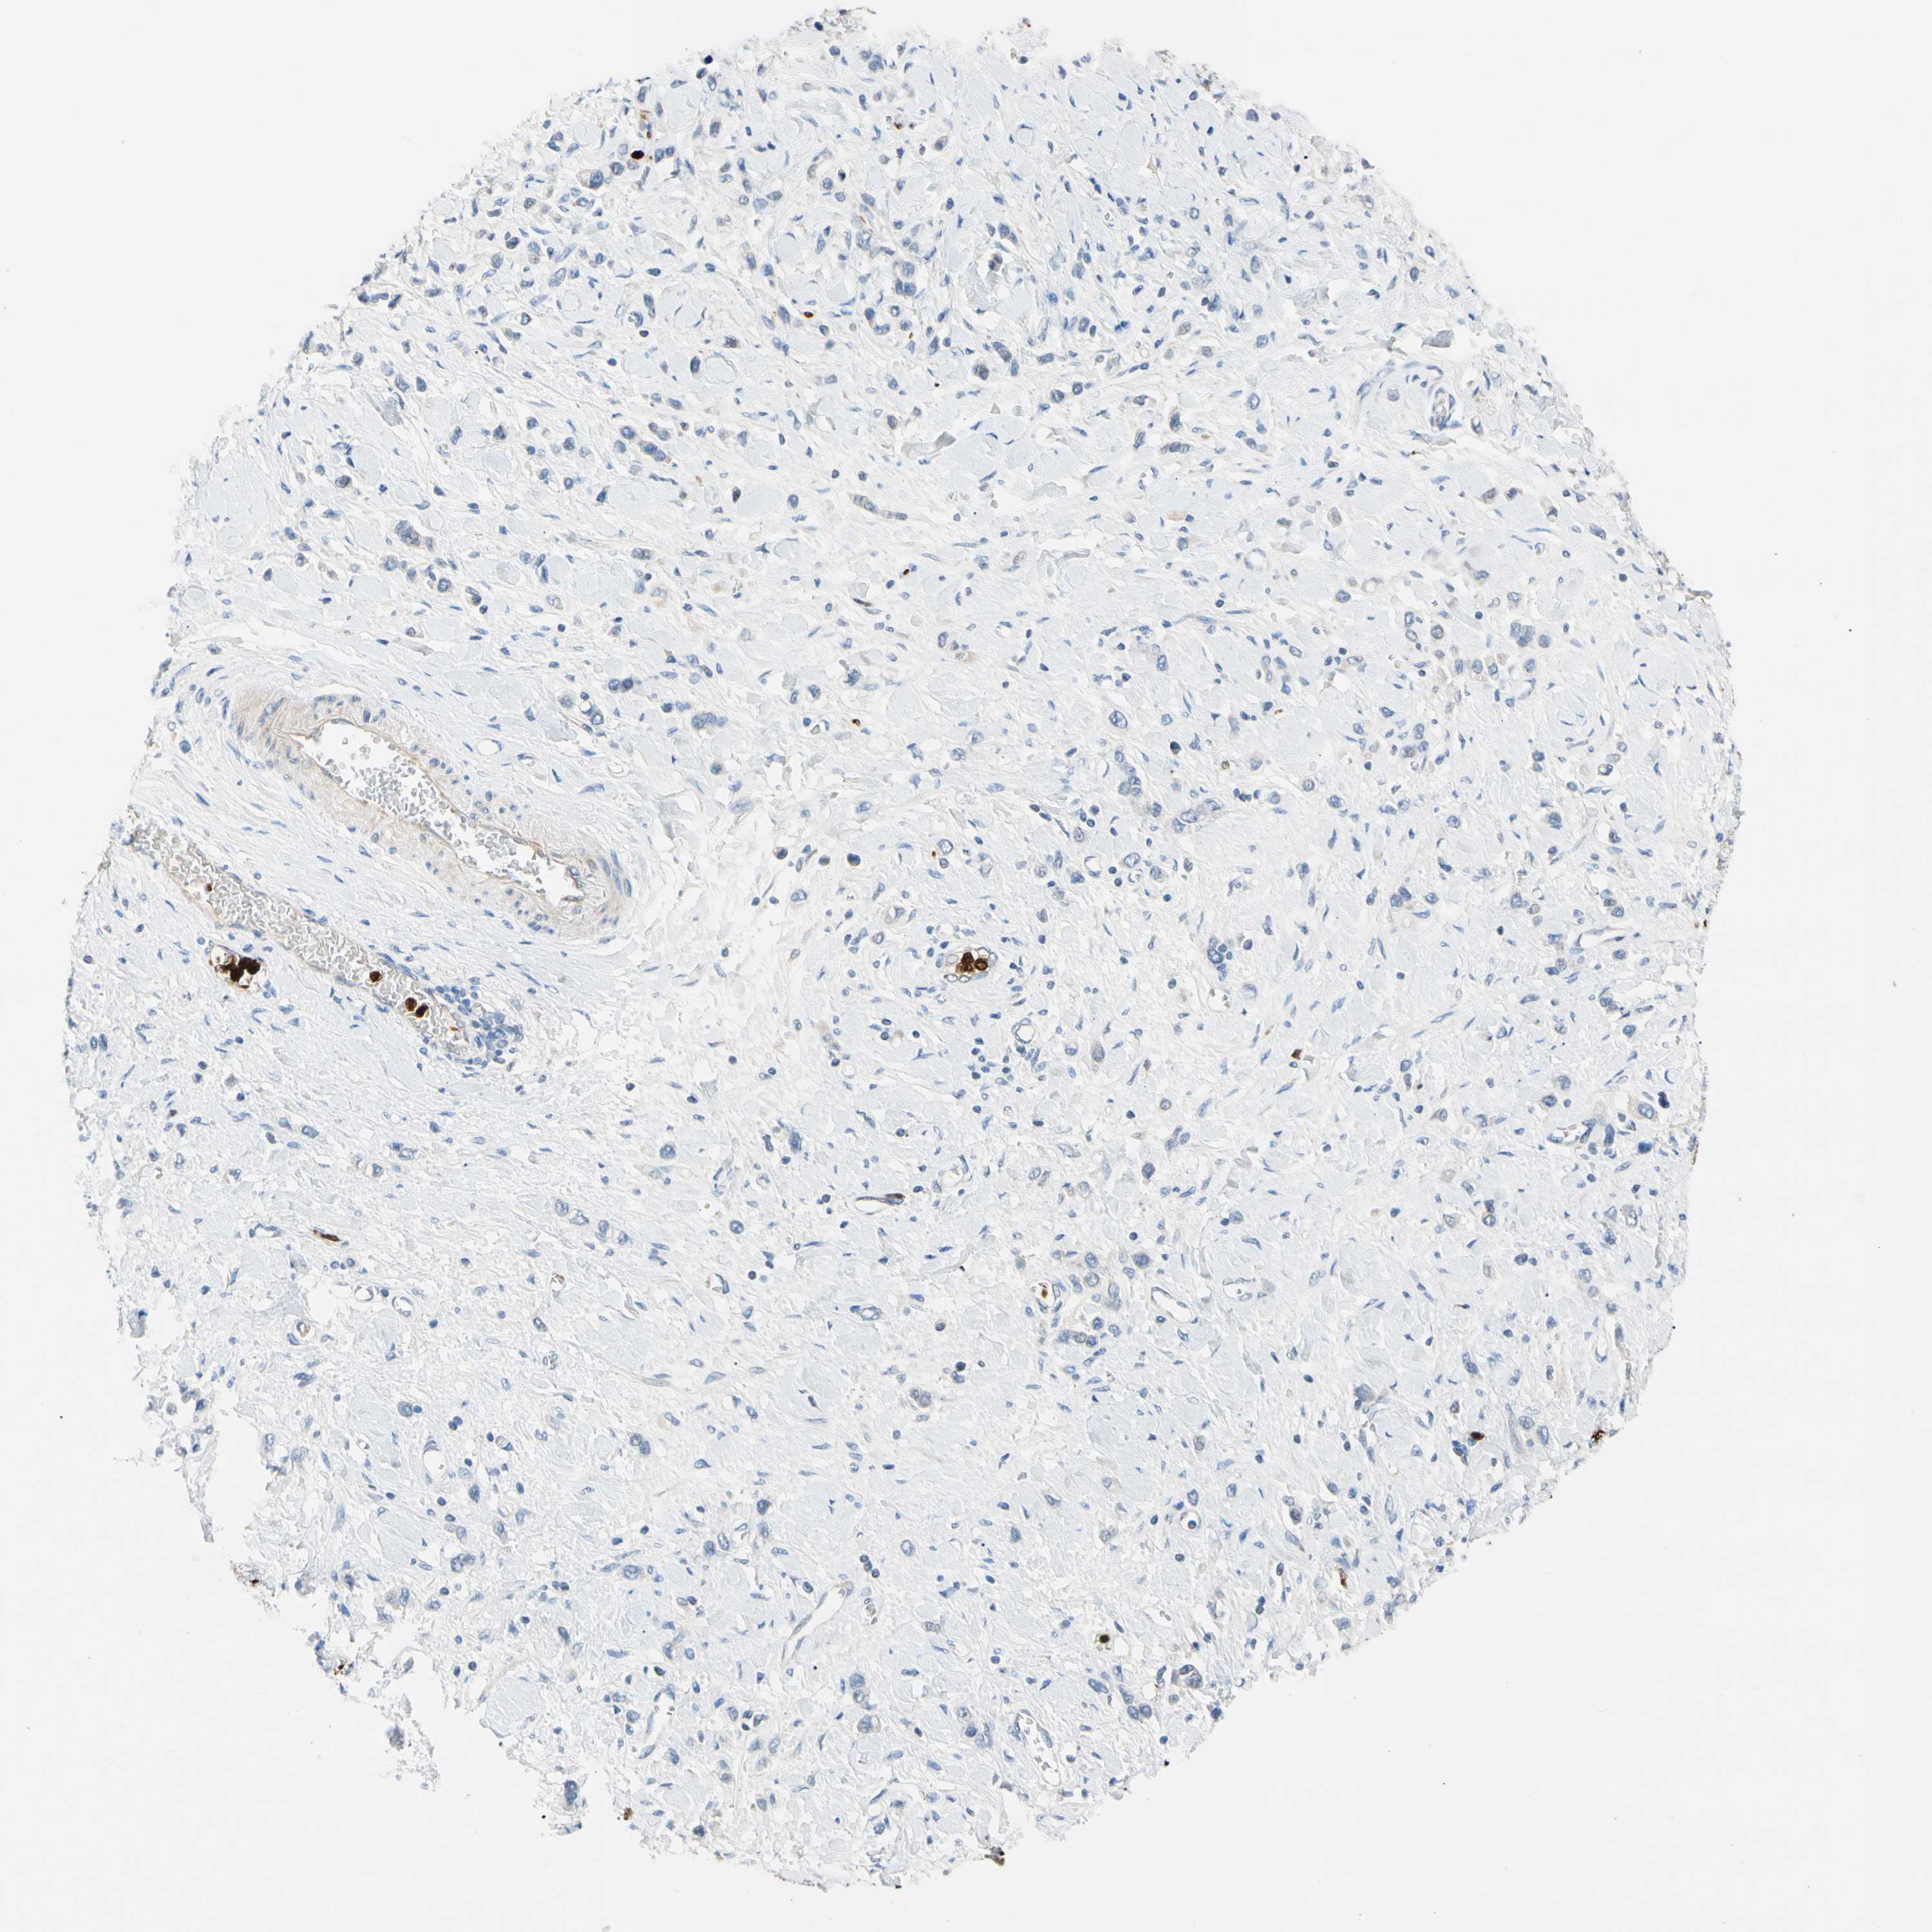

STOMACH CANCER - Protein expressioni

A mouse-over function shows sample information and annotation data. Click on an image to view it in a full screen mode. Samples can be filtered based on level of antibody staining by selecting one or several of the following categories: high, medium, low and not detected. The assay and annotation is described here.

Note that samples used for immunohistochemistry by the Human Protein Atlas do not correspond to samples in the TCGA dataset.

Antibody stainingi

Antibody staining in the annotated cell types in the current human tissue is reported as not detected, low, medium, or high, based on conventional immunohistochemistry profiling in selected tissues. This score is based on the combination of the staining intensity and fraction of stained cells.

Each image is clickable and will lead to virtual microscopy that enables deeper exploration of all samples and also displays staining intensity scores, fraction scores and subcellular localization as well as patient and tissue information for each sample.

Antibody HPA008052

Antibody CAB010277

Staining

High

Medium

Low

Not detected

Intensity

Strong

Moderate

Weak

Negative

Quantity

>75%

75%-25%

<25%

None

Location

Nuclear

Cytoplasmic/membranous

Cytoplasmic/membranous,nuclear

Adenocarcinoma, NOS

Adenocarcinoma, High grade